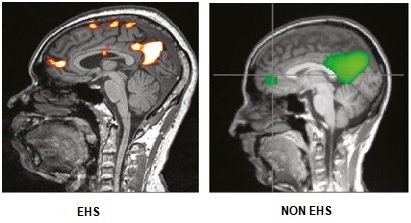

All ten patients had abnormal functional MRI brain scans. The abnormality was often described as hyper connectivity of the anterior component of the default mode in the medial orbitofrontal area. Other abnormalities were usually found. Regular MRI studies of the brain were mostly unremarkable in these patients.